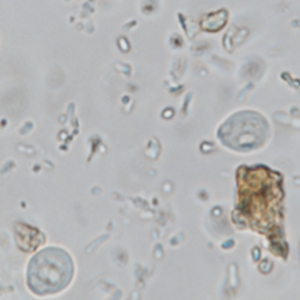

Les kystes de Chilomastix mesnili sont piriformes et de petite taille (6 à 10 μm), à paroi fine et réfringente. Ils présentent un noyau ainsi qu’un organite juxtanucléaire (cytostome) où se loge le flagelle; néanmoins cette structure est difficilement visualisable (Garcia, 2021). Le contenu du kyste est davantage visualisé lors de l’utilisation d’hématoxyline ferrique.

Le diagnostic différentiel comprend les autres kystes de protozoaires (notamment de petits kystes de flagellés et amibes). La distinction se fait sur la morphologie des noyaux, leur nombre, et la taille du kyste (Garcia, 2021). Une coloration à l’hématoxyline ferrique peut être utile pour visualiser les détails cytoplasmiques. Une coproculture permet de faire évoluer les kystes en trophozoïtes et d’améliorer le diagnostic.